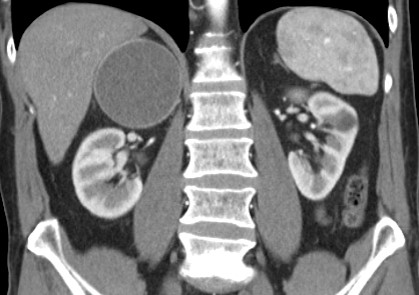

Is time for an interesting adrenal case!! Middle aged man with history of melanoma 🟡 What is your diagnosis? 🟢 What would you recommend?

Is time for an interesting adrenal case!! Middle aged man with history of melanoma

🟡 What is your diagnosis?

🟢 What would you recommend?